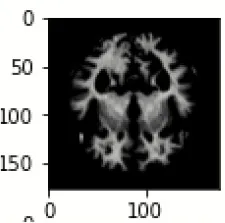

The database used in this study consists of a total of 6,200 AD images that are retrieved from the Kaggle database. It comprises grayscale images of 896 MD, 64 Mod D, 3,200 ND, and 1,966 VMD images, with a dimension of (208 × 176 × 3) pixels. The dataset for evaluation is divided in such a way that 80% of the image samples are utilized for training the model and the remaining 20% are utilized for testing the model (Filipovych et al., 2011). Figure 2 shows the database of MRI images. Table 2 shows the publicly available AD dataset.

FIGURE 2

www.frontiersin.org

Figure 2. Alzheimer's disease: (A) M.D, (B) Mod.D, (C) N.D, and (D) V.M.D.